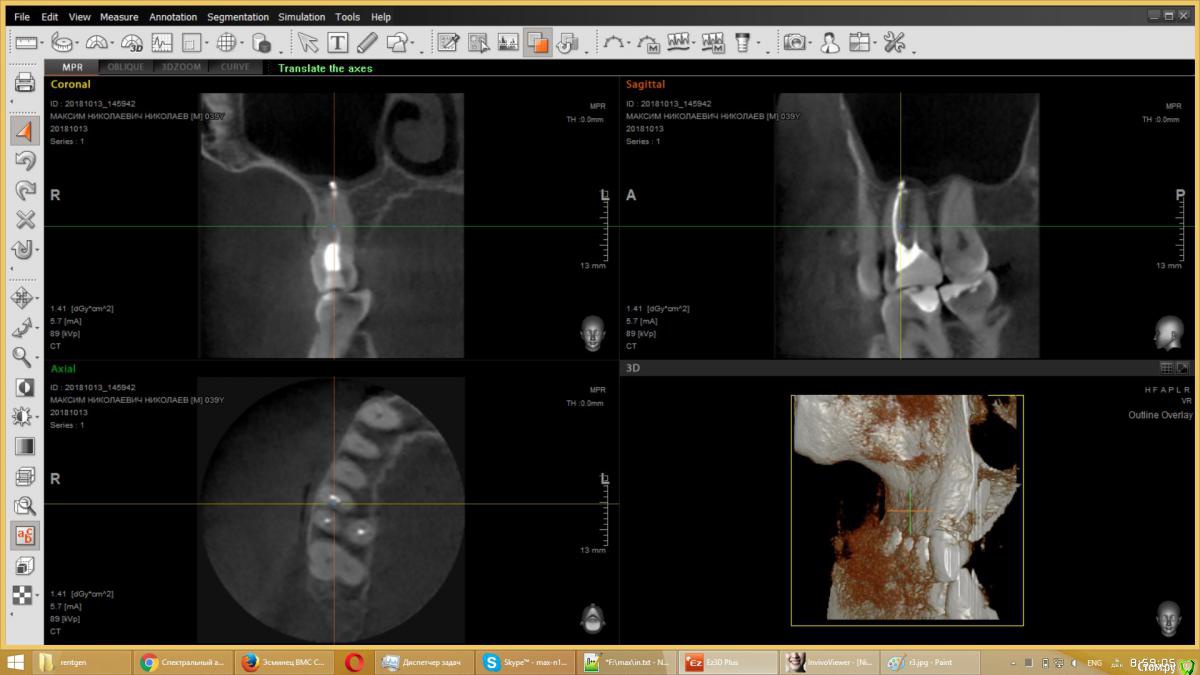

usilitel Опубликовано 4 декабря, 2018 Поделиться Опубликовано 4 декабря, 2018 (изменено) 10 месяцев назад депульпировали верхнюю 6-ку, с тех пор мучаюсь неврологическими симптомами (онемение, давление, зуд). На снимке с зубом всё нормально. Возможная причина - небольшое количество материала вышло в гайморову пазуху (но осталось под слизистой). Я думаю что этот материал мог задеть нерв, отсюда и симптомы. Зуб вырывать врачи отказываются, т.к. показаний к удалению нет. К тому же может не помочь.Хочу вынуть материал из гайморовой пазухи, но непонятно как это сделать. Прошу совета.Возможный варианты:1) Оставить всё как есть. Меня этот вариант не устраивает, т.к.: 1) материал может быть причиной проблем с неврологией, и его удаление может решить проблему. 2) зуб все равно рано или поздно придется удалять, не хотелось бы чтобы после удаления зуба в организме осталось инородное тело.2) Вынуть эндоскопом сверху. ЛОР сказал что так сделать нельзя, т.к. поскольку материал под слизистой - сверху его не увидишь. Правда можно содрать слизистую и всё-таки достать материал, но вред от такого действия многократно превысит пользу.3) При удалении зуба вынуть материал снизу. По словам хирурга - стоматолога - это сделать нереально, т.к. для этого придется разрезать перегородку, отделяющую гайморову пазуху, и она потом сама не заживёт.4) Надеяться, что матерал сам выйдет вместе с зубом при удалении зуба. Вариант крайне маловероятный, т.к. при удалении зуба материал практически наверняка останется в пазухе.5) Распломбировать канал, протолкнуть материал дальше в гайморову (чтобы он вышел за слизистую), а потом вынимать сверху эндоскопом. Не уверен что найду терапевта который согласится это сделать.6) Сразу после удаления зуба протолкнуть материал дальше в гайморову (чтобы он вышел за слизистую), а потом вынимать сверху эндоскопом. Не уверен что найду хирурга который согласится это сделать. PSЗуб мне не жалко, всё равно рано или поздно его надо будет удалять. Изменено 4 декабря, 2018 пользователем usilitel Ссылка на комментарий

usilitel Опубликовано 6 декабря, 2018 Автор Поделиться Опубликовано 6 декабря, 2018 выкладываю снимки Ссылка на комментарий